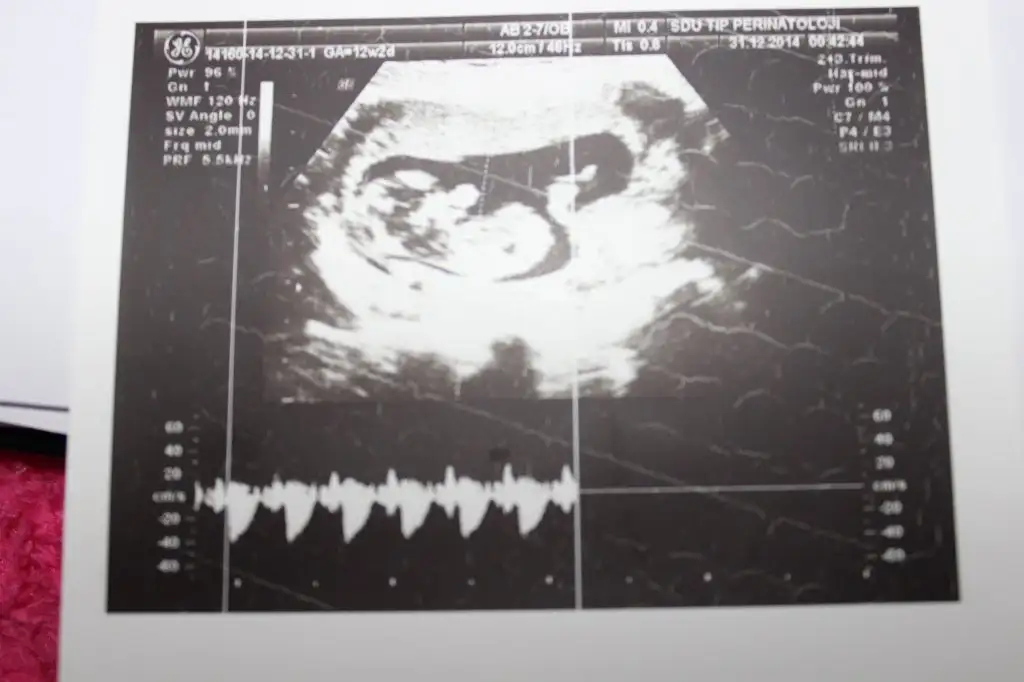

dr soylemeden siz gorun genital nub teorisi ( bebegin cinsiyeti)

IMG_1301.webp IMG_1302.webp IMG_1303.webp IMG_1306.webp

Kiz dedigim foto on haftalikmis zaten canm o haftada hepsi kiz gibi gorunur bilseydim kucuk derdim son fotodan belli erkek bebegin geliyor bence